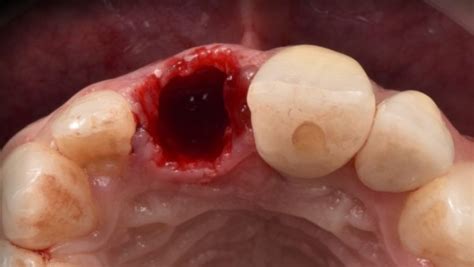

- Alveolitis seca: se caracteriza por la ausencia del coágulo de sangre en el alveolo. A veces la cavidad alveolar está hueca y seca, de ahí el nombre de alveolitis seca, con el hueso claramente visible. Alveolitis seca: se presenta inmediatamente después de la extracción, sin sangrado significativo.

- Exposición del hueso: En casos de alveolitis seca, el coágulo de sangre se pierde, dejando el hueso expuesto en el alveolo. A veces la cavidad alveolar está hueca y seca, de ahí el nombre de alveolitis seca, con el hueso claramente visible.

- Hueso visible en el alveolo.